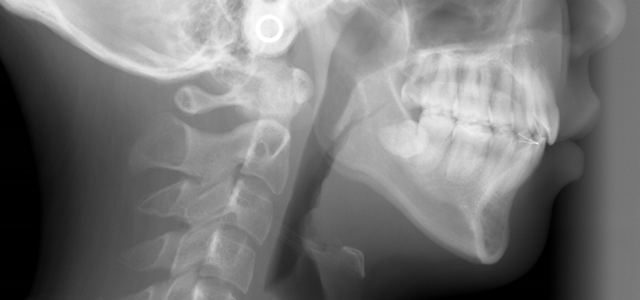

矯正前 パノラマX線

主訴 前歯で物が咬めない、歯並びの凸凹、出っ歯を治したい

年齢 20代

治療法 上下顎マルチブラケット装置、歯科矯正用アンカースクリュー

抜歯の有無 上顎左右側第一小臼歯、下顎左右側第二小臼歯

治療期間 1年10ヶ月